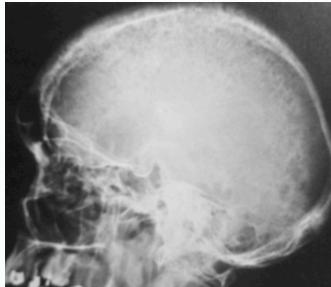

- Skull: âsalt & pepperâ appearance

Salt-and-pepper-spots-in-skull

- Salt and pepper skull